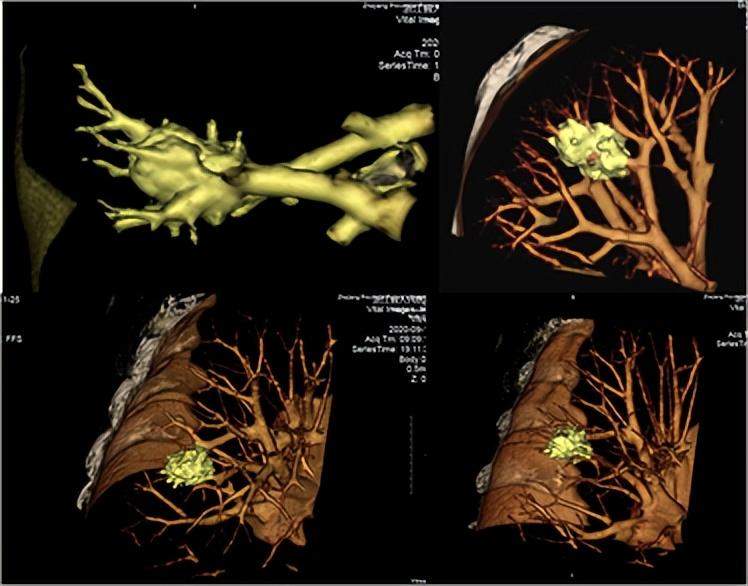

三维重建CT平扫影像

CT平扫+三维重建是在影像学检查技术螺旋CT扫描的基础上,通过计算机将扫描采集到的图像、数据进行重建,从而产生直观、立体、高质量的三维图像。该技术的优点在于扫描速度快、时间短、图像清晰且立体。将三维重建引入临床的辅助诊断、治疗,检查结果从平面转为立体化,可以提高诊断准确性和效率。如果需要手术,也是用这种技术明确肿瘤位置。价格一般在800-1000元。